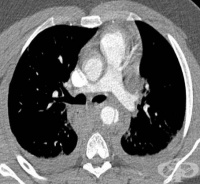

S25 Травма на кръвоносните съдове на гръдния кош

Честотата на травми на медиастиналните съдове сред преживелите тежка гръдна травма е 1,4-5%. Пострад...

S25.0 Травма на торакалната част на аортата

Евентуална повреда, на тази част на аортата, която се намира в гръдната кухина се нарича травма на т...

S25.4 Травма на белодробни кръвоносни съдове

Травмите на белодробни кръвоносни съдове са редки и изключителни трудно лечими. Най-често травма на ...